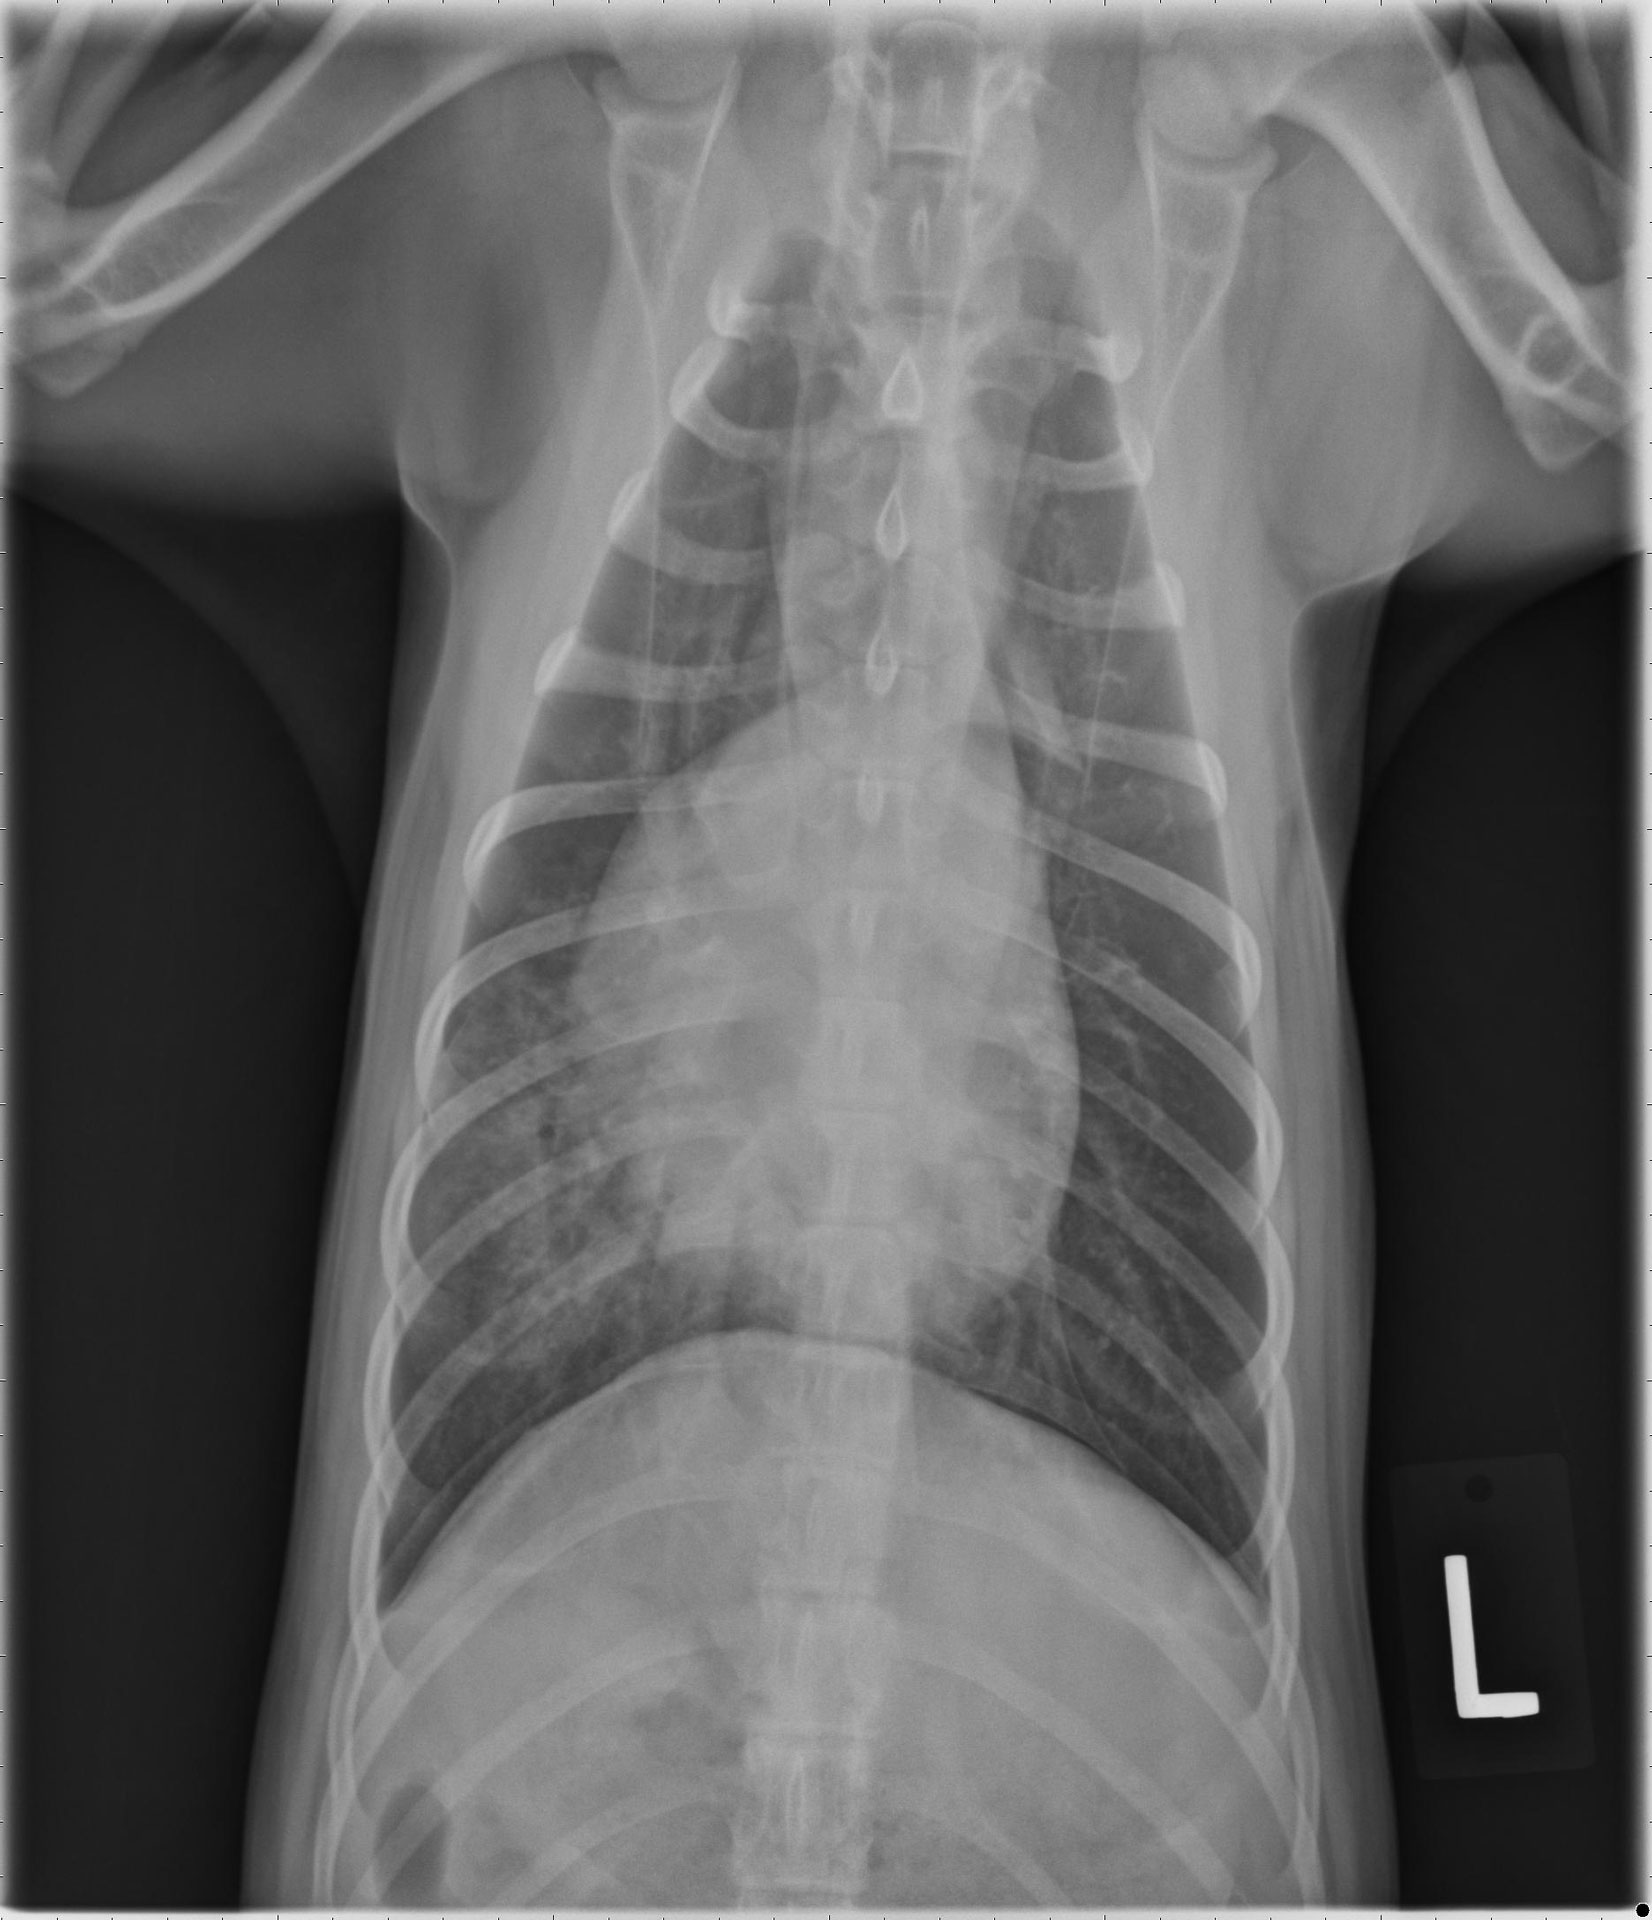

Chest Xray on day 4. Diffuse alveolar pattern. Download Scientific Diagram Alveolar Pattern Common causes of this pattern include pulmonary edema, inflammation, fibrosis, and tumour. Pulmonary alveolar edema is a particular pattern of pulmonary edema where most of the fluid build up is in the alveolar spaces. An alveolar pattern is defined by the existence of more or less broad portions of the lung more opaque than normal due to partial or complete. Alveolar Pattern.

Diffuse alveolar pattern over bilateral lung fields. Pulmonary... Download Scientific Diagram Alveolar Pattern Common causes of this pattern include pulmonary edema, inflammation, fibrosis, and tumour. Pulmonary alveolar edema is a particular pattern of pulmonary edema where most of the fluid build up is in the alveolar spaces. When there is disease in the. Alveolar lung disease (ald) refers to filling of the airspaces with fluid or other material (water, pus, blood, cells, or. Alveolar Pattern.

Chest radiograph showing bilateral interstitialalveolar pattern. Download Scientific Diagram Alveolar Pattern Learn how to identify and differentiate alveolar pattern on chest radiographs and ct scans, which is the imaging representation of various. When there is disease in the. The detection and characterization of airspace disease in the lungs. Pulmonary alveolar edema is a particular pattern of pulmonary edema where most of the fluid build up is in the alveolar spaces. Common. Alveolar Pattern.

Chest radiograph showing bilateral interstitialalveolar pattern. Download Scientific Diagram Alveolar Pattern From a histopathologic standpoint, the most severe manifestation of acute lung injury, diffuse alveolar damage (dad), involves damage to all three layers of the alveolar wall and. Common causes of this pattern include pulmonary edema, inflammation, fibrosis, and tumour. When there is disease in the. Alveolar lung disease (ald) refers to filling of the airspaces with fluid or other material. Alveolar Pattern.